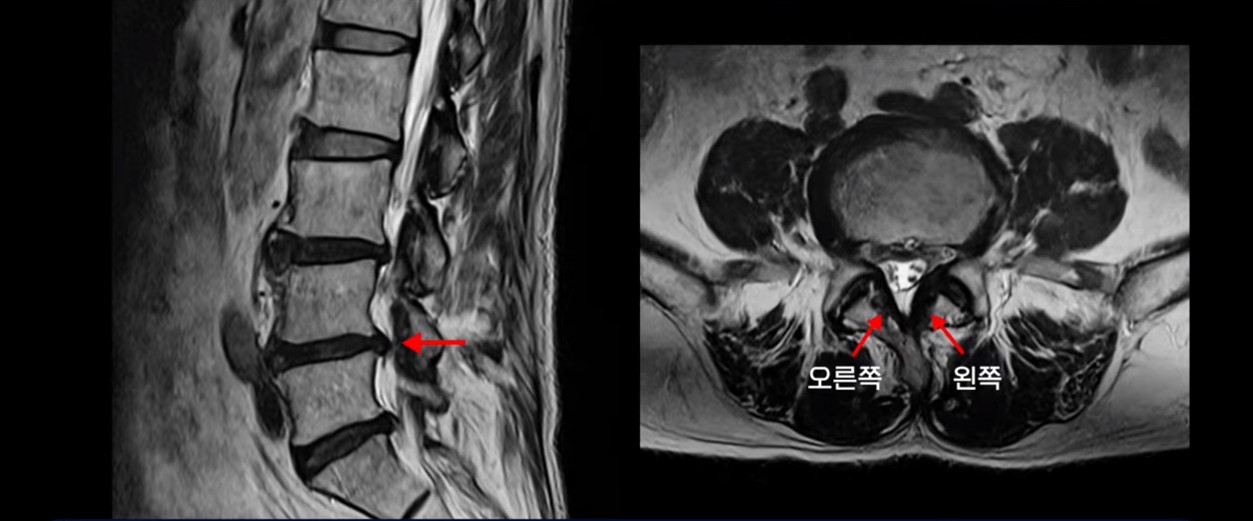

이분 MRI를 보면서 간단히 설명 드린 후 어떻게 허리에서 신경이 눌려서 발목이 마비된 환자가 수술 없이 치료가 될 수 있는 건지, 또 치료는 구체적으로 어떻게 하는 건지 자세히 설명 드리겠습니다.

이분은 허리디스크 탈출도 있고 중심성 협착도 있습니다.

4번 5번 중심성 협착을 보면 왼쪽 황색인대가 오른쪽에 비해 많이 두꺼워져 있습니다.

이 밀려나온 디스크는 최근 발생한 게 아니고 오래 전 발생하여 이미 굳어버린 디스크 수핵으로 보입니다. 보시다시피 앞에서는 밀려나온 디스크 뒤쪽에서는 두꺼워진 황색 인대가 신경을 눌러 발목마비가 온 걸로 보입니다.